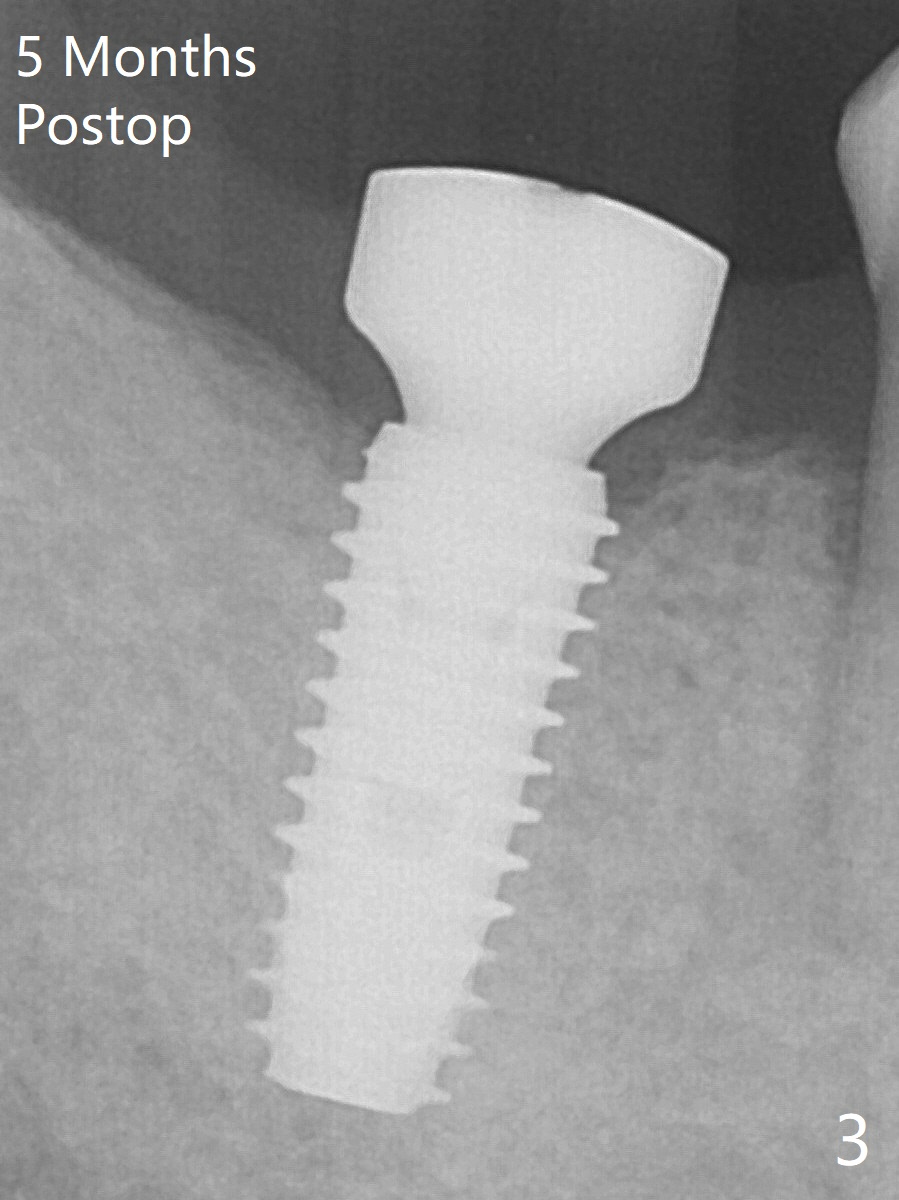

The leukoplakia at the sites of #31 and 32 is most likely related to smoking and the supraerupted teeth #1 and 2 (Fig.0 ^).  After osteotomy for 11.5 mm at #31 (Fig.1), it appears that the bone height is not as much as expected.  The last two drills for sequential osteotomy are 4.3x13 and 4.8x11.5 mm.  A 5x11.5 mm UF implant is placed slightly subcrestal with insertion torque > 50 Ncm (Fig.2).  Following placement of 6.5x2 mm healing abutment, the opposing tooth needs adjustment for height.  Orthodontic intrusion of the opposing tooth is scheduled 2 days later.  It is accidental to find root fracture of the mesial root of the tooth #30 (Fig.1 <).  There is minimal bone resorption coronally 5 months postop (Fig.3).  A provisional is fabricated at #31 to assist in intrusion of the tooth #2.  A crown is cemented 11.5 months postop (Fig.4); the leukoplakia at #31 seems to lessen.  The tooth #30 is lost during the pandemic, followed by looseness of the crown and abutment at #31.  When the complex is reseated, the occlusal scheme is changed, suggesting incomplete seat of the abutment earlier (Fig.5).